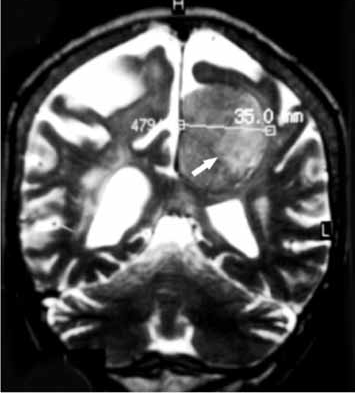

Paciente com 60 anos de idade se apresenta com quadro de cefaleia moderada há 3 meses, e há 15 dias discreta redução da atenção, moderada hemiparesia direita e vertigens. Não tem antecedentes mórbidos; o exame clínico é normal e o exame neurológico confirma os achados. A ressonância magnética é apresentada a seguir.

Com esses elementos, qual a sua primeira impressão diagnóstica?